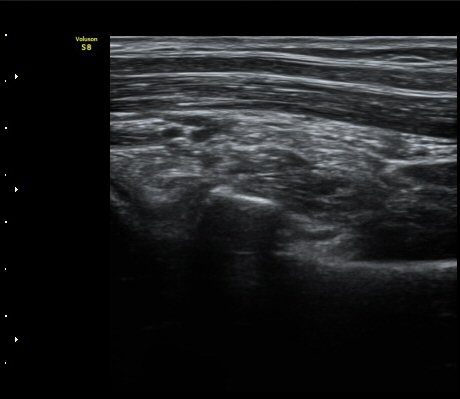

ÆÈ²ÞÄ¡ ³»Ãø¿¡¼­ ½ÃÇàÇÑ ¿ä°ñµÎ Á¾´Ü¸é°Ë»ç¿¡¼­ ¿ä°ñµÎ ÇÇÁú°ñÀÇ ºÒ±ÔÄ¥º¯È­(irregularity)°¡

°üÂûµÇ¾î ¼Õ»óÀÌ ÃßÁ¤µÊ(±×¸² 3)

¿ä°ñµÎ Ⱦ´Ü¸é°Ë»ç¿¡¼­ ƯÀÌ ¼Ò°ßÀ» º¸ÀÌÁö ¾ÊÀ½(±×¸² 4)

¾Æ·§ÆÈÀ» µ¹¸®¸é¼­ ¿ä°ñµÎ Ⱦ´Ü¸é°Ë»ç ½Ã ¿ä°ñµÎ ÇÇÁú°ñ ¿¬°á¼º ¼Ò½ÇÀÌ °üÂûµÊ(±×¸² 5)